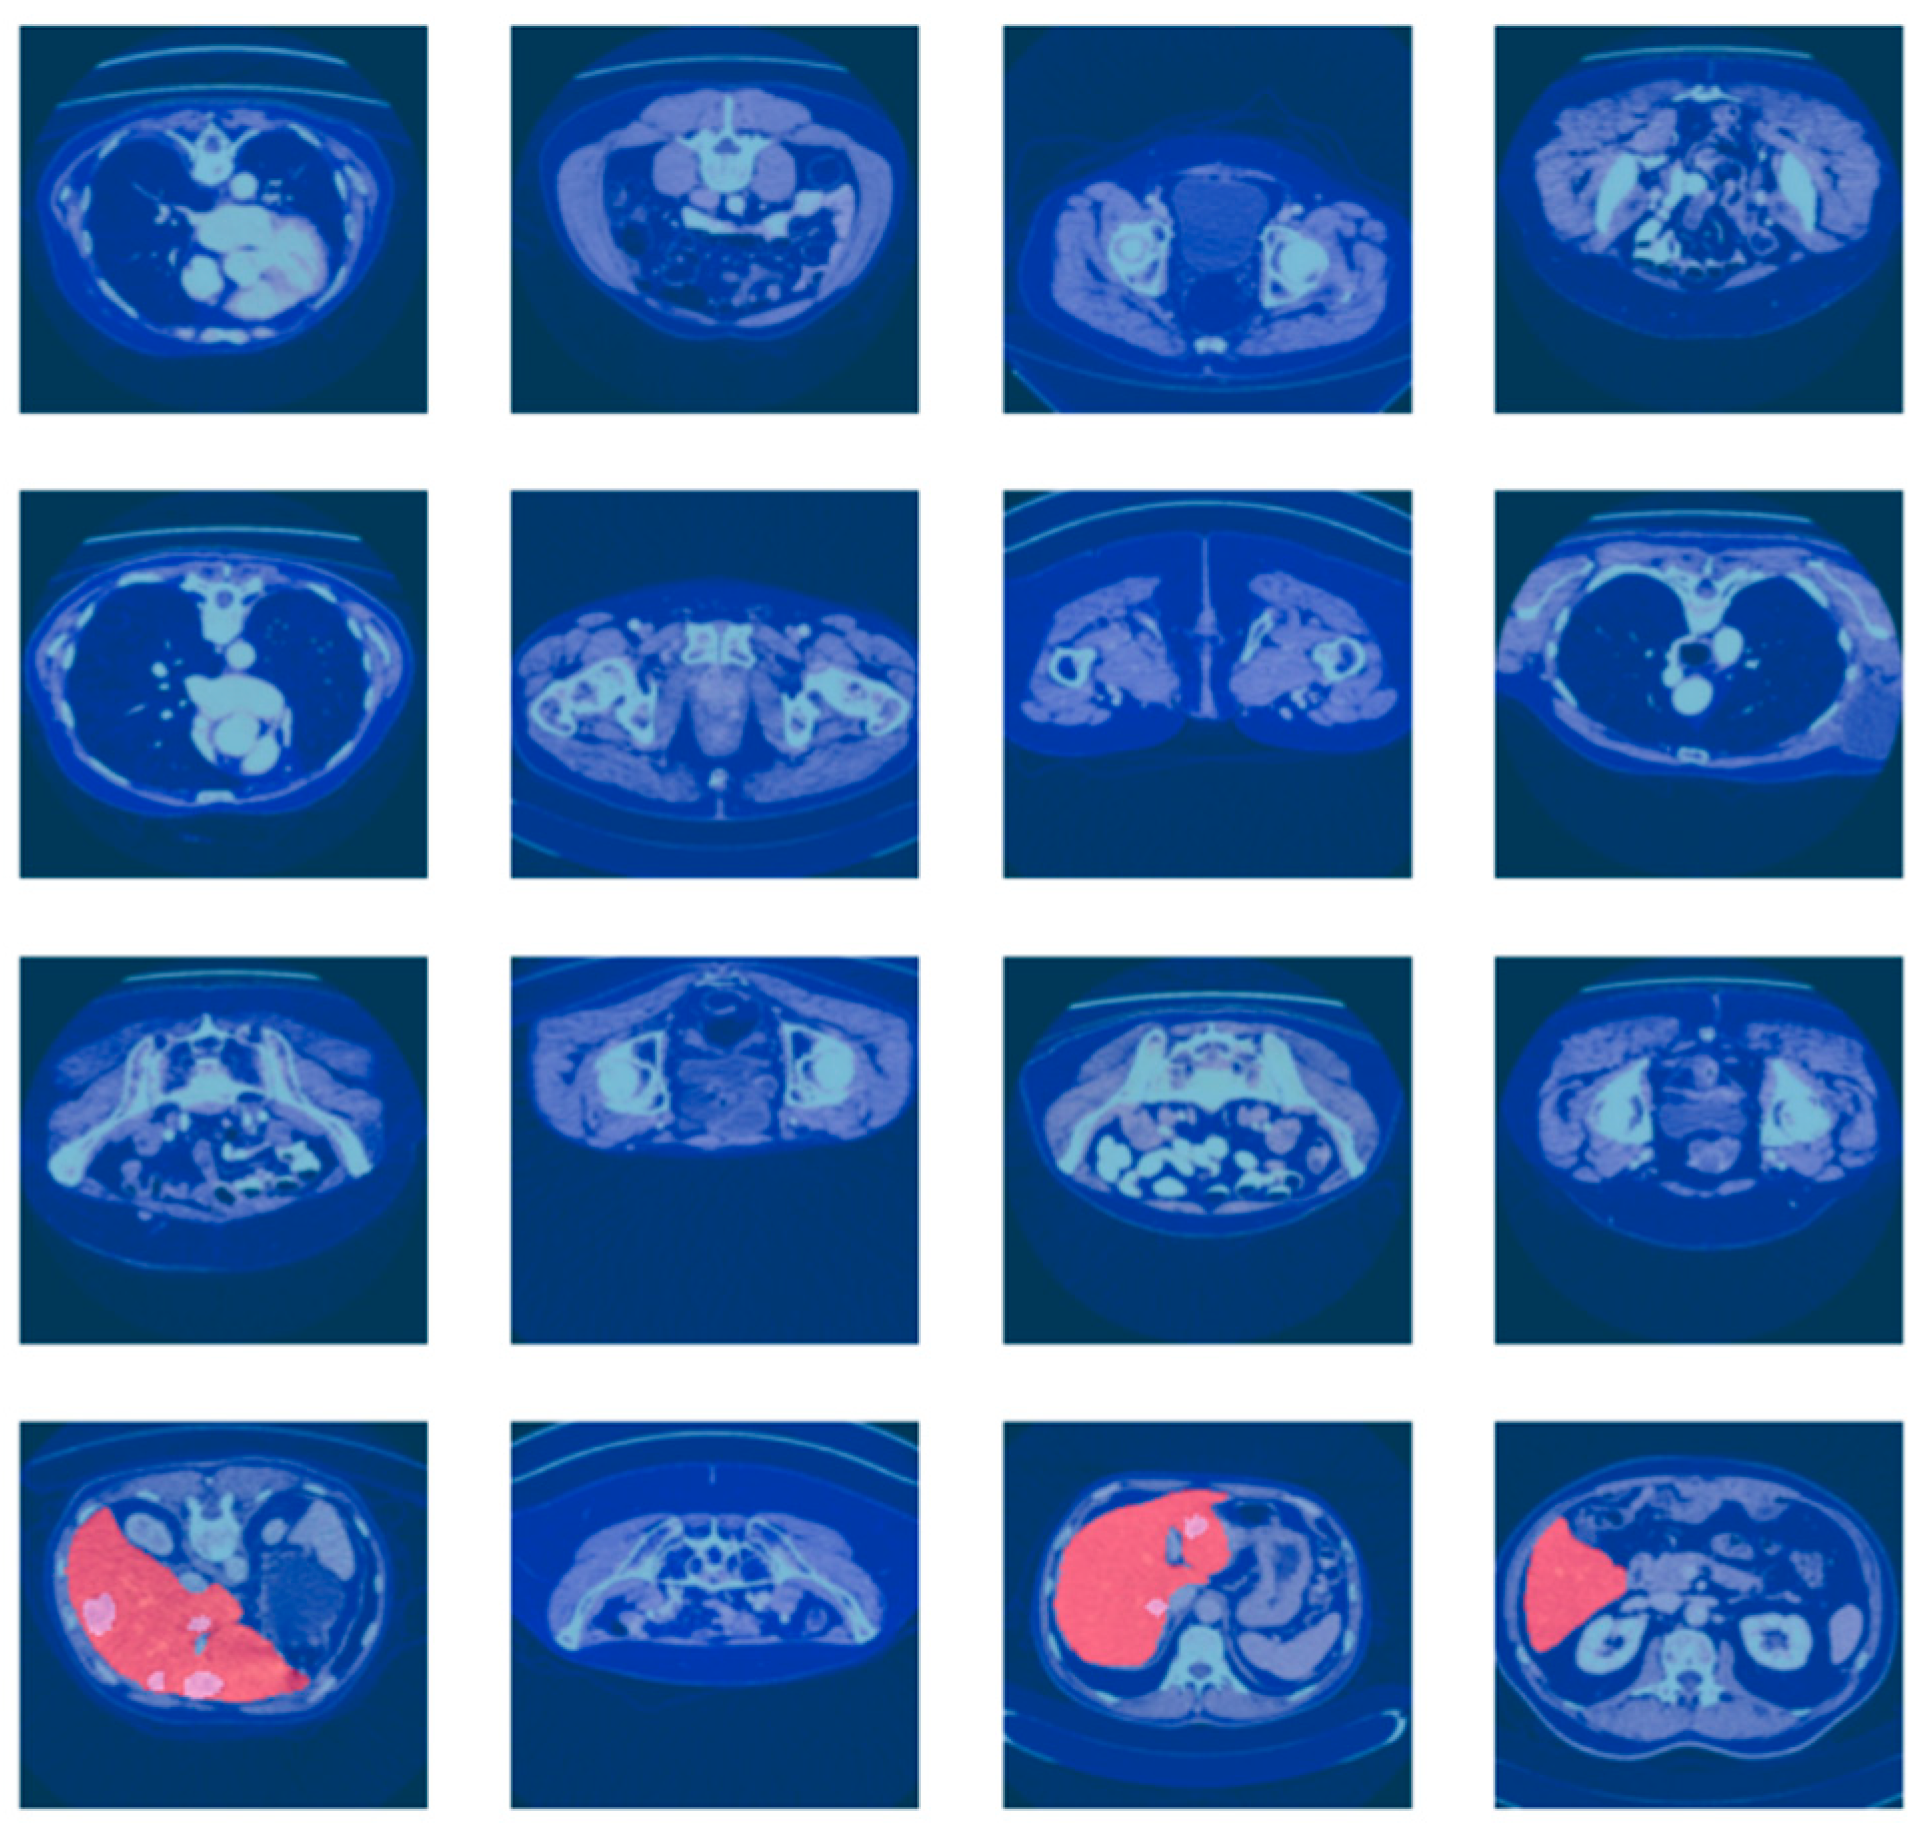

3.1. Dataset Description

3.2. Dataset Preprocessing